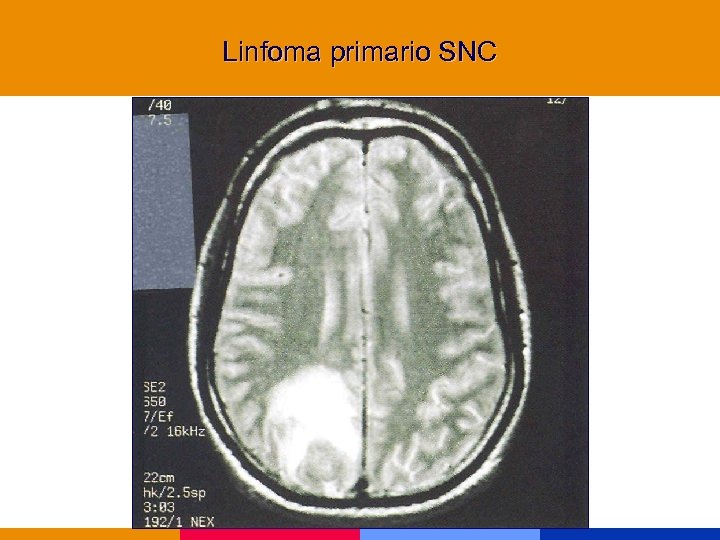

Linfoma primario SNC

Linfoma primario SNC